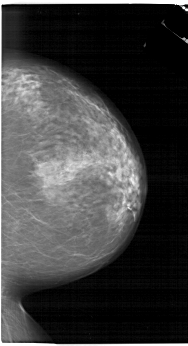

A_1657_1.RIGHT_MLO

RIGHT_MLO LINES 6871 PIXELS_PER_LINE 4036 BITS_PER_PIXEL 12 RESOLUTION 43.5 NON_OVERLAY